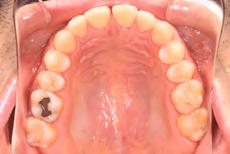

Clinical evaluation showed a mild Class III skeletal pattern with a constricted maxilla, mildly dolichofacial and straight

profile (Figure 1). Full adult dentition was present with all third molars extracted. Maxillary and mandibular incisors were normoclined. The maxillary midline coincided with the facial midline, and the mandibular midline was 2 mm to the right of the facial midline. There was a 2 mm to 5 mm lateral open bite on the right side from the second molar to the lateral incisor, and the maxillary occlusal plane was canted to the left of the interpupillary line. A lateral tongue thrust into the open bite was noted on swallow.

The right side was in posterior crossbite and there was an edge-to-edge anterior bite with wear on the maxillary central incisors. Mild gingival recession was noted, but soft tissue was generally within normal limits. CBCT analysis found no radiographic evidence of osteoarthritis in the TMJ joints, nor osseous or apical pathology involving the maxillary or mandibular teeth. His airway was not constricted. Initial report from the myofunctional therapist indicated that the patient never developed a mature swallow sequence and had a bilateral posterior tongue thrust.

Figure 1. Initial records.